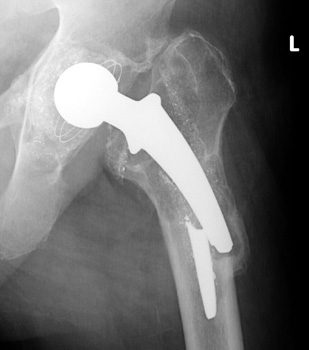

Broken femoral stem with remodeling of the lateral femoral cortex.